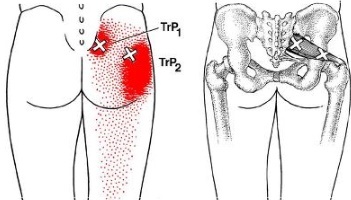

이상근은 엉덩이와 다리를 연결하는 고관절을 단단하게 붙잡아 주는 근육으로 이 밑으로 허리뼈에서 나와 다리까지 이어지는 좌골신경이 지나는데, 이상근이 딱딱하게 굳고 염증이 생기거나 부종이 생기는 등 변화가 생기면서 좌골신경을 누르거나 자극해 통증이 생깁니다. 이상근증후군의 원인은 정확히 밝혀지지 않았으나 엉덩이부터 허벅지 뒤쪽으로 내려가면서 통증이 뻗치는 증상은 허리디스크와 매우 흡사합니다.

이상근증후군이 왜 나타나는지는 정확하게 밝혀지지 않았습니다. 하지만 증상은 허리디스크로 인해 나타나는 다리 통증과 매우 흡사합니다. 주로 엉덩이 부분에 통증이 심하게 나타납니다. 엉덩이부터 허벅지 뒤쪽으로 내려가면서 통증이 뻗치는데 허리를 굽히거나 오랜 시간 앉아 있을 때, 오래 앉아 있다 일어설 때 쥐어짜는 듯한 통증이 나타나기도 합니다.